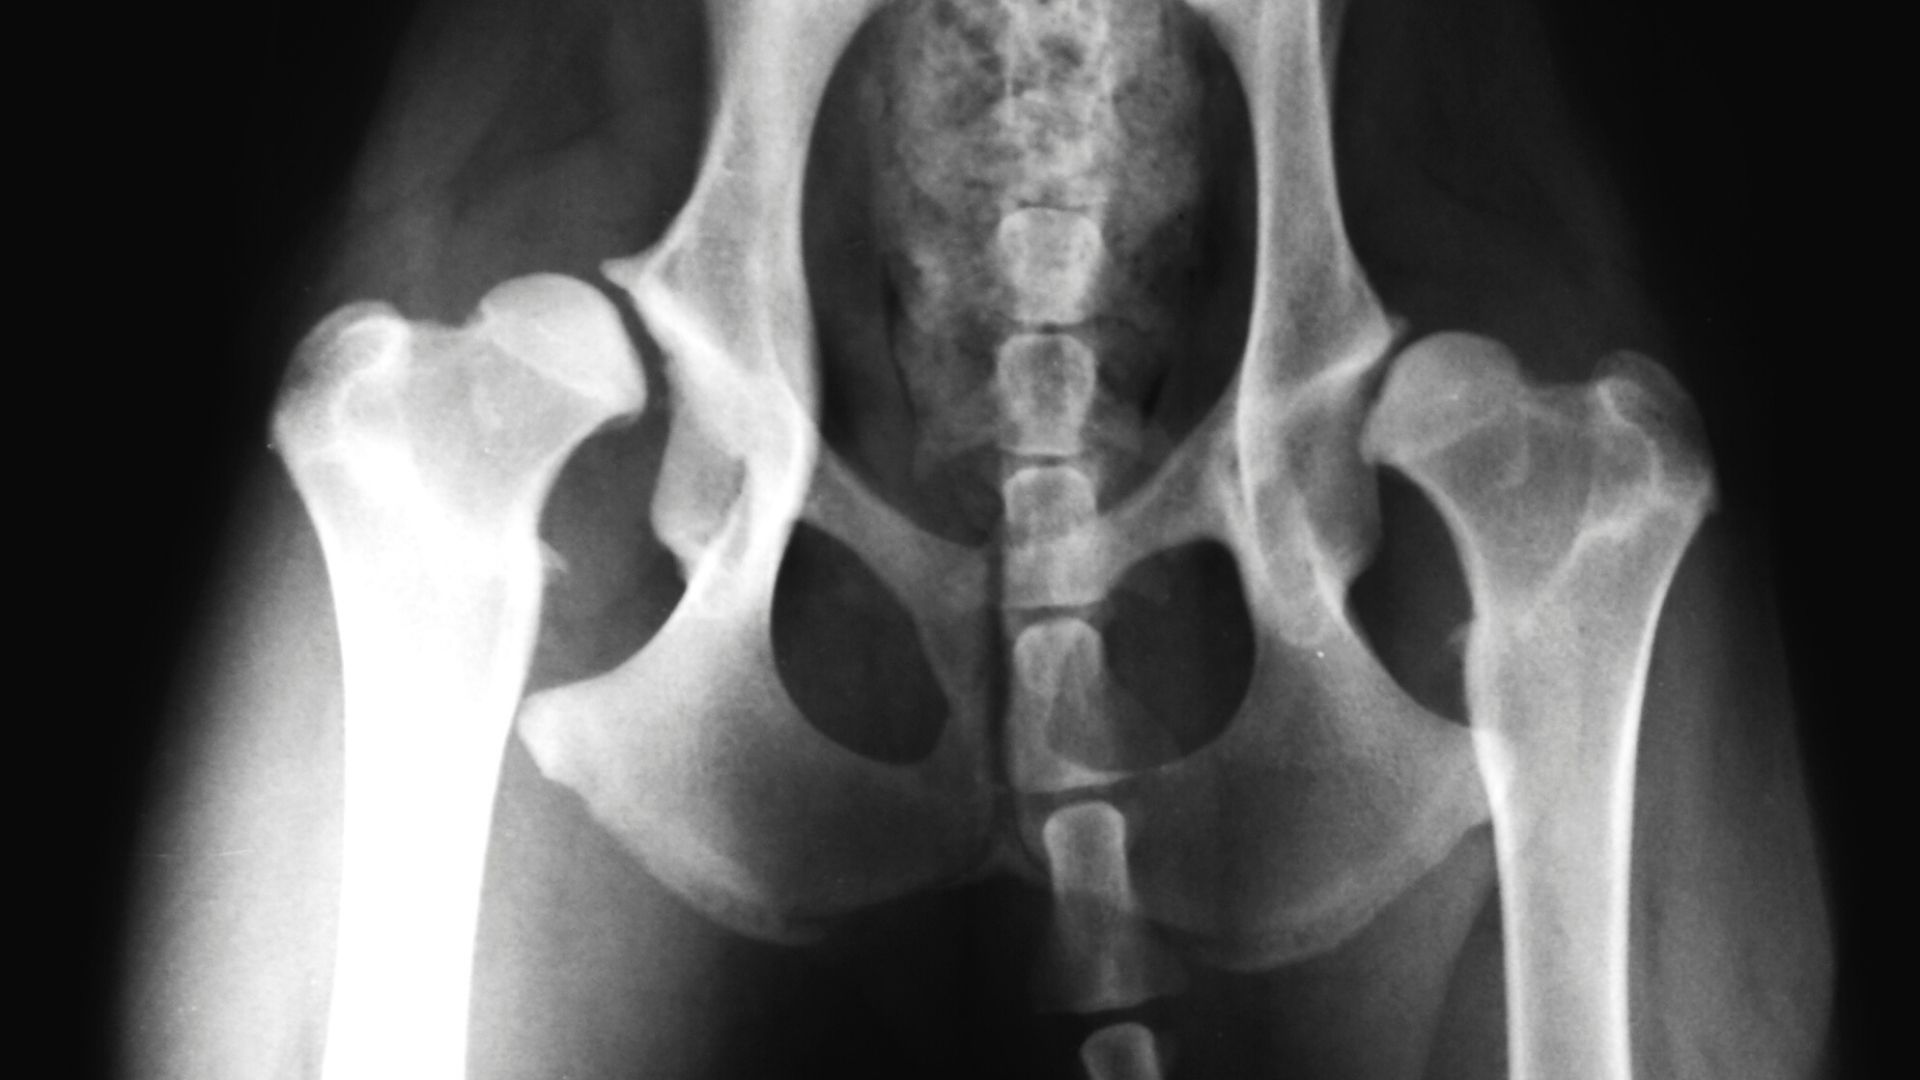

Canine hip dysplasia or hip dysplasia in dogs is a condition where that results in the loosening of a dogâs hip joint. It can occur during the growth stage in Puppies, and since it is commonly seen in certain large dog breeds, it is known to be a hereditary condition.

Similarly, hip dysplasia can also be due to trauma. It is very important to differentiate between hereditary and traumatic hip dysplasia, and a veterinary surgeon would be able to diagnose after a thorough orthopaedic evaluation.